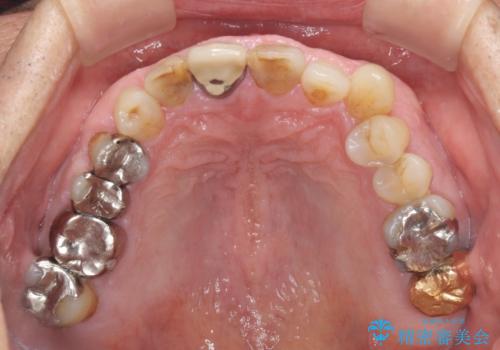

- 前歯がぐらつくことを主訴にご来院された患者様です。ご本人は抜歯と考えており、インプラント以外の治療をご希望でした。しかしながらぐらついていた原因は、古い差し歯が取れかけていたことでした。

遠方から通院されること、仕事上短期間で治療したいとのことを考慮して、残っている歯はかなり小さいものの、保存すべきと判断して当日処置から行いました。

西日本から新幹線でご来院された患者様です。前歯は都内の医院でやりたいとのことで、はるばる通院してくださいました。通院回数が最小限になるよう工夫しました(1回あたりの時間は長くなります)。

残っている歯が小さいと、差し歯はぐらつきやすくなりますが、その形態によっては抜歯を回避できることがあります。